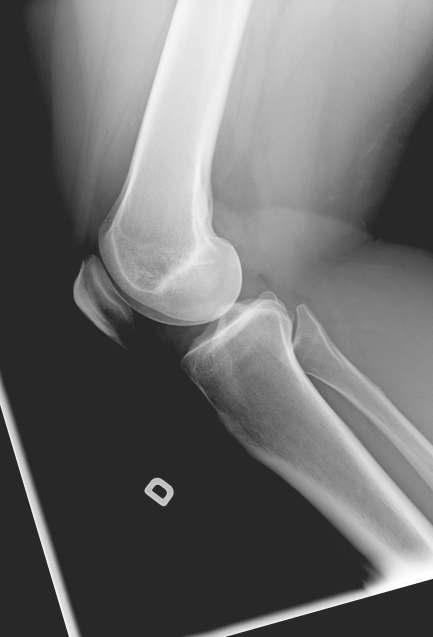

Carlos Grovas-Badrena, MD, FIAIME, CIME, CMLE

Cirugía Reconstructiva Ortopédica

Cursó sus estudios de bachillerato en Premédica, en Georgetown University, Washington, D.C Estudió en la Escuela de Medicina de la Universidad de Puerto Rico (UPR), Recinto de Ciencias Médicas y fue parte del primer grupo de residentes en la Residencia de Ortopedia de este Recinto, lo cual lo motivó a escoger la especialidad de Ortopedia. Ha tenido la dicha de practicar más de 9,000 procedimientos de reemplazo total de articulaciones y continuó la práctica de su primer reemplazo total de cadera y rodilla en Puerto Rico, en el Recinto de la UPR. Del mismo modo, orientó, adiestró y amplió los conocimientos a residentes de Ortopedia en esta subespecialidad en dicho recinto

El doctor Grovas-Badrena continuó desarrollando su especialidad en Cirugía Reconstructiva en pacientes con artritis en hospitales afiliados a la Escuela de Medicina de Harvard, Boston, MA. Además, fue presidente de facultad en el Hospital Pavia en Hato Rey por seis ocasiones y director del Departamento de Ortopedia en dicha institución por 34 años

En el ambiente deportivo fue Director Médico del equipo de baloncesto, los Mets de Guaynabo, y brindó sus servicios como ortopeda en los Juegos Panamericanos (COPAN), Centroamericanos y del Caribe, y al Equipo Nacional de Baloncesto El especialista trabajó como Perito Consultor Ortopédico en la Fiscalía Federal desde el año 1995. Brindó sus conocimientos como Consultor Ortopédico en el Departamento de Rehabilitación Vocacional por 20 años y ejerció como Asesor Ortopédico en el Sistema de Retiro de Empleados del Gobierno por 18 años. Más tarde, fue Consultor Ortopédico en la Honorable Comisión Industrial durante 15 años. El galeno ha realizado múltiples publicaciones para periódicos y revistas, entrevistas radiales y de televisión, conferencias en varias universidades y foros legales de nuestro país, confirmando así su gran trayectoria El cirujano ortopédico realizó un Fellow en el International Academy of Independent Medical Evaluators (IAIME, por sus siglas en inglés) Lo han reconocido como Cirujano Distinguido de San Juan y de parte de la American Medical Association, además de haber recibido el Physician Recognition Award.

Grovas-Badrena identifica varios factores que hoy en día son retos en su campo de especialidad y en la medicina,

como lo es el exilio de doctores debido a las aseguradoras de planes médicos en Puerto Rico “Hoy día, el reto principal en mi campo es el dilema crónico con las aseguradoras de planes médicos, lo cual hace que se desplacen fuera de Puerto Rico más de 500 doctores en medicina anualmente”, menciona.

Las áreas de oportunidad que identifica en su profesión para continuar sirviendo a sus pacientes son practicar las evaluaciones médicas independientes y brindar servicios de la especialidad de Cirugía Reconstructiva Ortopédica a nivel estatal y federal para distintas entidades en la isla. De igual forma, reconoce los asuntos medicolegales “Los casos medicolegales incluyen toda alteración de salud y daño al paciente que son producidos por una causa externa o ajena y que dejan residuos en el cuerpo humano. Luego de culminar el tratamiento por una lesión sufrida, la persona es examinada por un evaluador médico independiente certificado para determinar residual de incapacidad y se redacta un informe medicolegal, con el cual el reclamante es compensado Es un campo interesante, ocupa gran parte de mi tiempo, requiere constante investig ación médica y continúa evolucionando”, afirma el especialista.

Para el cirujano, su mayor compromiso con la salud y el bienestar de sus pacientes se fundamenta en brindar tratamiento pro-bono a los pacientes que carecen de seguro médico privado o gubernamental. “El bienestar de mis pacientes siempre ha sido mi meta. Se basa en crear un ambiente con atención y seguimiento individualizado por personal adiestrado en intervenciones con impacto positivo. Así, mejora la calidad de vida del paciente con un desenvolvimiento independiente en actividades del diario vivir, fomentando el apoyo emocional, lo que influye en la adherencia al tratamiento”. El doctor Grovas reconoce la importancia de seguir utilizando de manera continua varios canales de comunicación con el fin de fomentar una relación segura con sus pacientes, lo que conlleva un impacto significativo a nivel físico, personal, familiar, social y laboral.

Para solicitar sus servicios, puede visitar su oficina en el Edificio Midtown Plaza, B-12, 420 Avenida Ponce de León, San Juan PR, 00918. Su horario es desde las 7:00 a.m. hasta las 12:00 p.m. Puede contactarlo al (787) 754-8642.